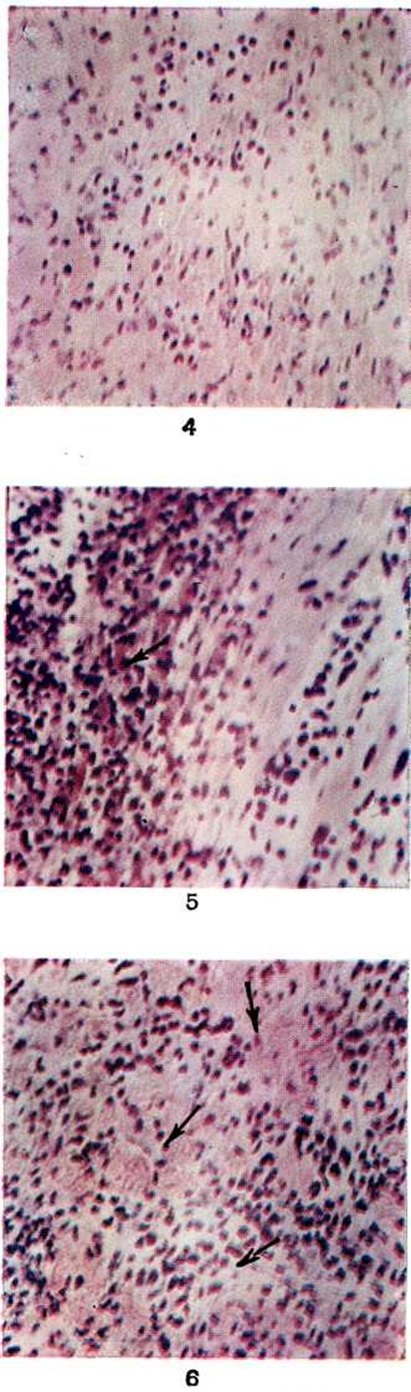

Общим для всех стадий, форм и морфологический разновидностей Миокардит является дряблость миокарда, охватывающая все его отделы, пестрота рисунка на разрезе, обусловленная скоплениями воспалительного инфильтрата, инъекцией терминального сосудистого русла, тяжами грануляционной и фиброзной ткани при хронический течении Миокардит В расширенных полостях сердца обнаруживаются сгустки крови, а при длительном течении Миокардит нередко пристеночные тромбы (рисунок 2). Такие тромбы особенно характерны для миокардита Абрамова — Фидлера.

Описанные изменения при длительном течении Миокардит дополняются гипертрофией миокарда, выраженной в стенках обоих желудочков, особенно левого.

Макроскопические изменения дают основание только для предварительного заключения о Миокардит; они всегда должны быть подтверждены гистологический исследованием разных участков миокарда. Учитывая частую мозаичность распространения воспалительного процесса в сердце, из передней и задней стенки обоих желудочков и межжелудочковой перегородки (с включением сосочковых мышц) вырезают не менее 6—8 кусочков размером 1,5—2 × 0,5 сантиметров.